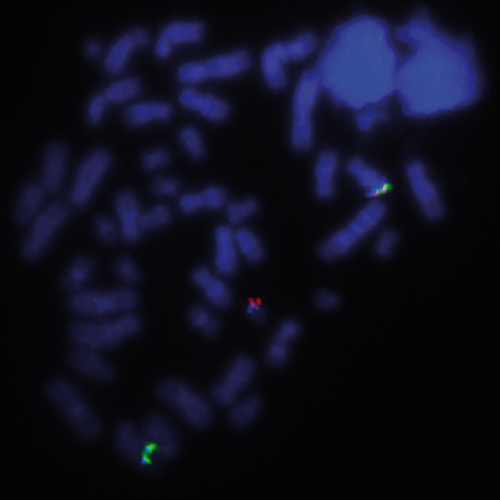

7q- (7q22; 7q36) hybridized to patient material showing a 7q36 deletion (1R2G). Image kindly provided by Prof. Jauch, Heidelberg.

Loss of a whole chromosome 7 or a deletion of the long arm, del(7q), are recurring abnormalities in malignant myeloid diseases. Most deletions are interstitial and there are two distinct deleted segments of 7q. The majority of patients have proximal breakpoints in bands q11-22 and distal breakpoints in q31-36. The CCAAT displacement protein CUX1 gene region is located in the 7q22 critical region. The 7q- specific FISH probe is optimized to detect copy number of 7q at 7q22 and at 7q36 simultaneously in a dual-color assay.